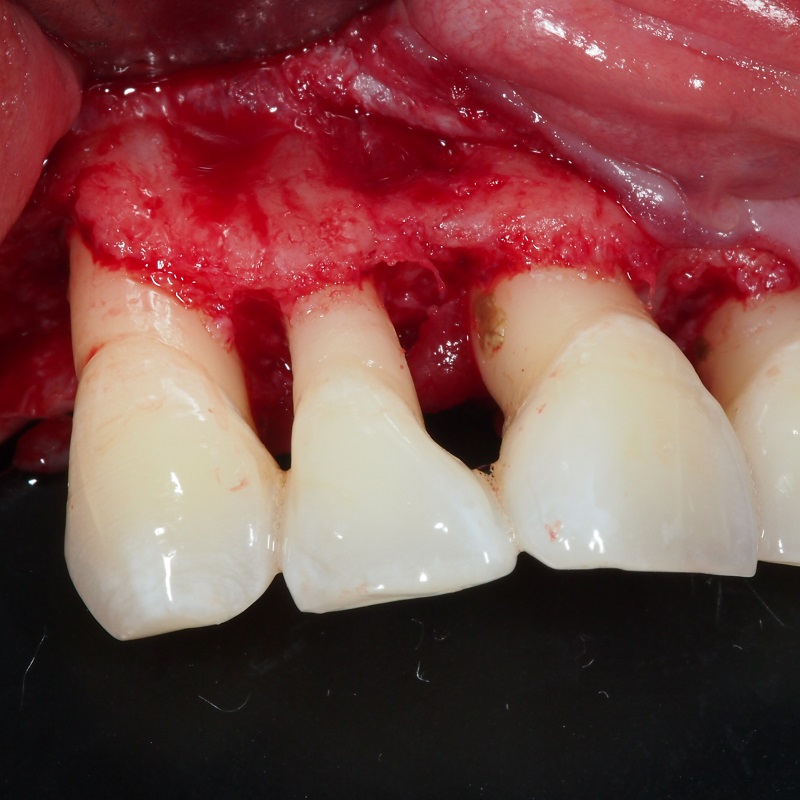

- Desbridamiento por colgajo

- Raspado de raíces dentales

- Desintoxicación de las raíces

La regeneración tisular guiada consiste en la aplicación quirúrgica de una membrana biocompatible para aislar y proteger el daño óseo y biomateriales de relleno para regenerar las estructuras de soporte de los dientes.